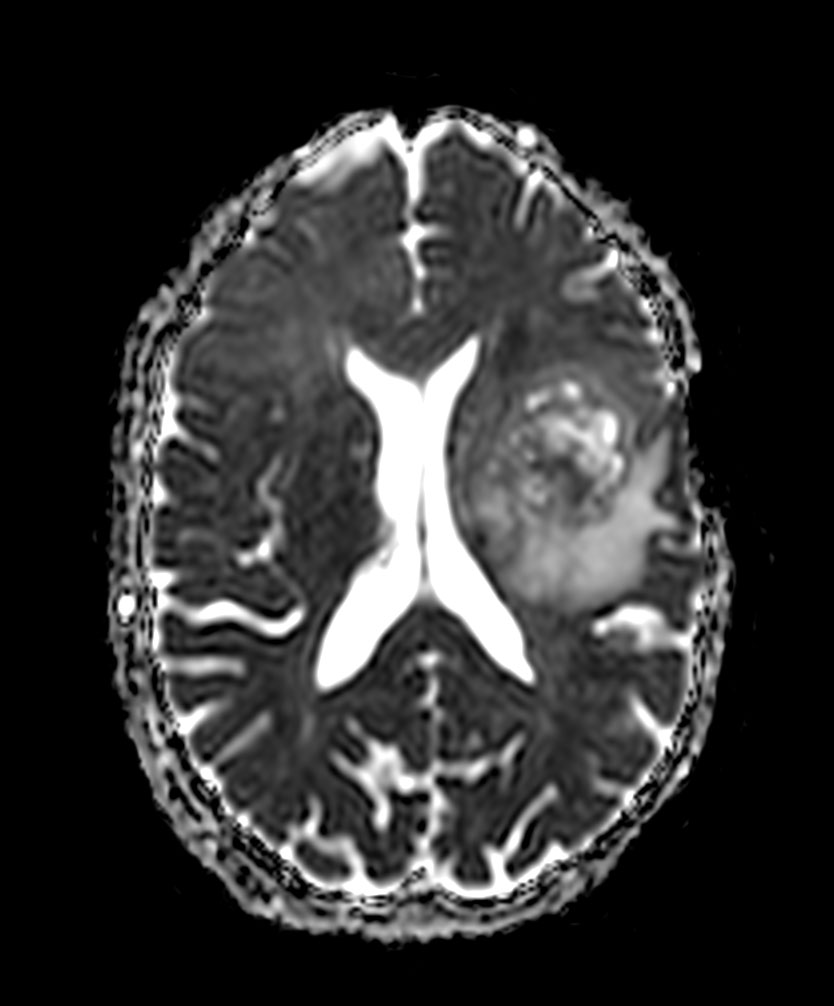

Axial DWI (b1000)